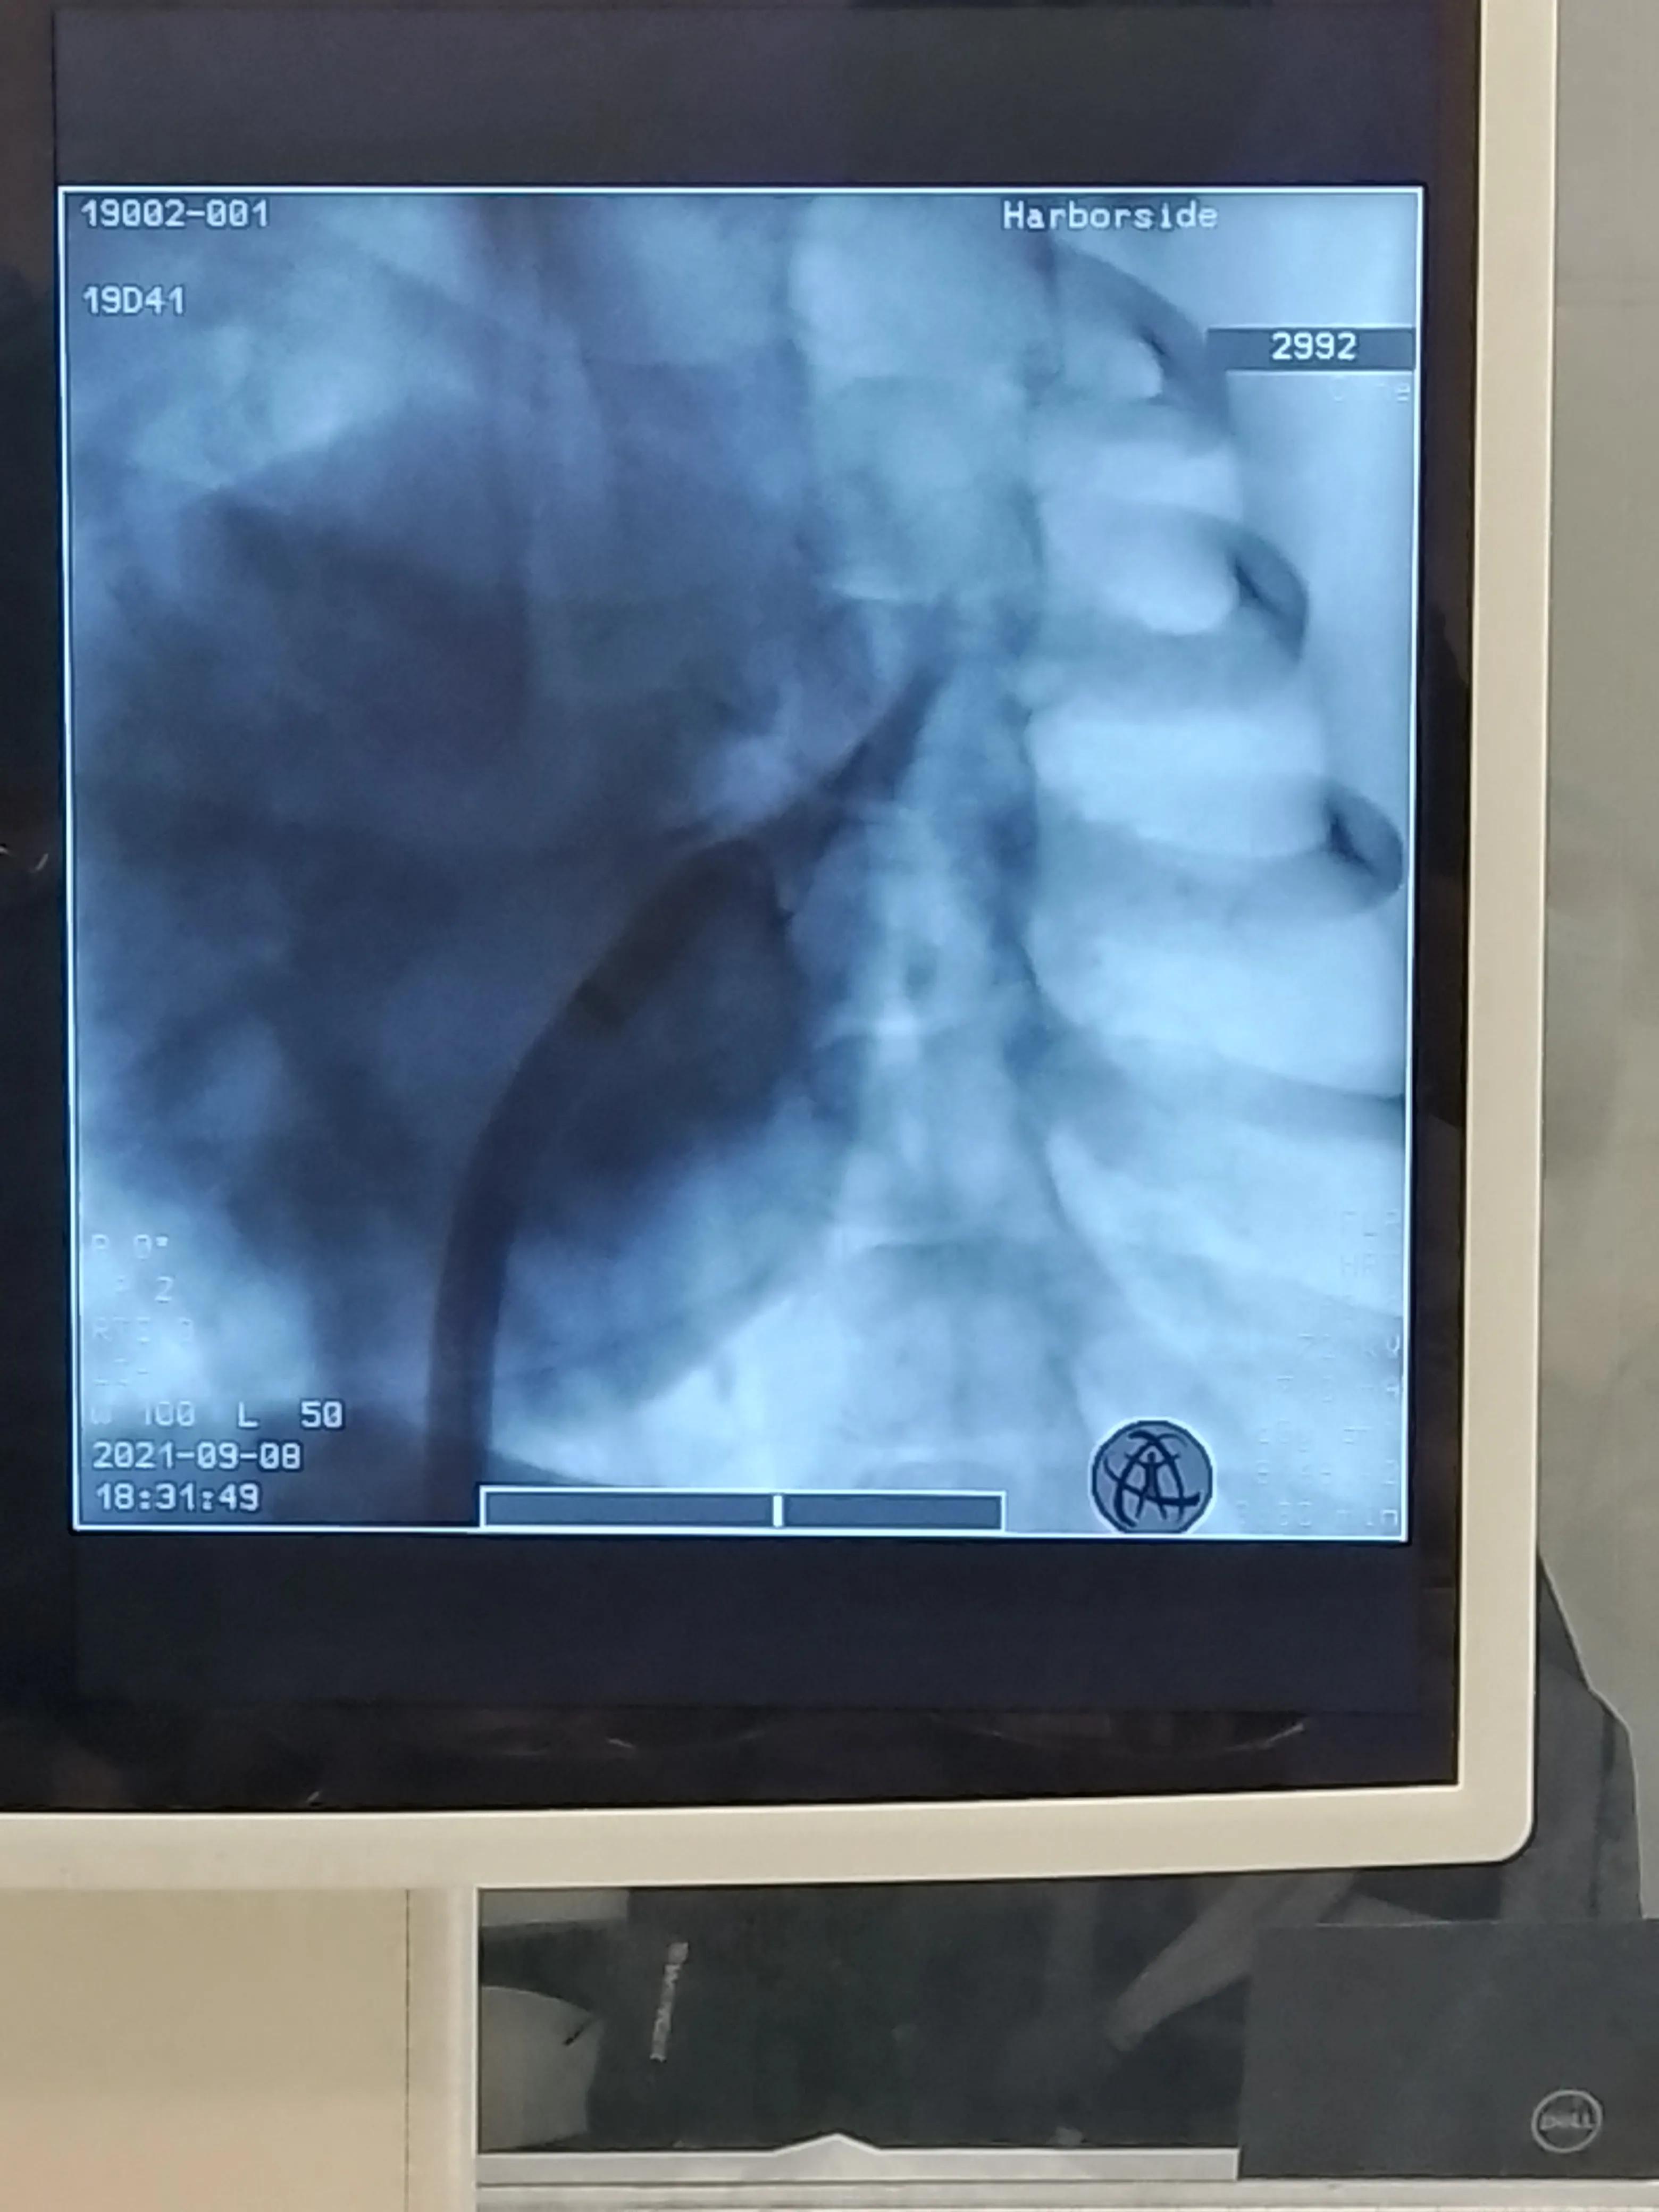

左肺静脉显影